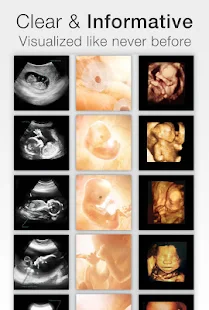

- Color and scan images

- More ultrasound images